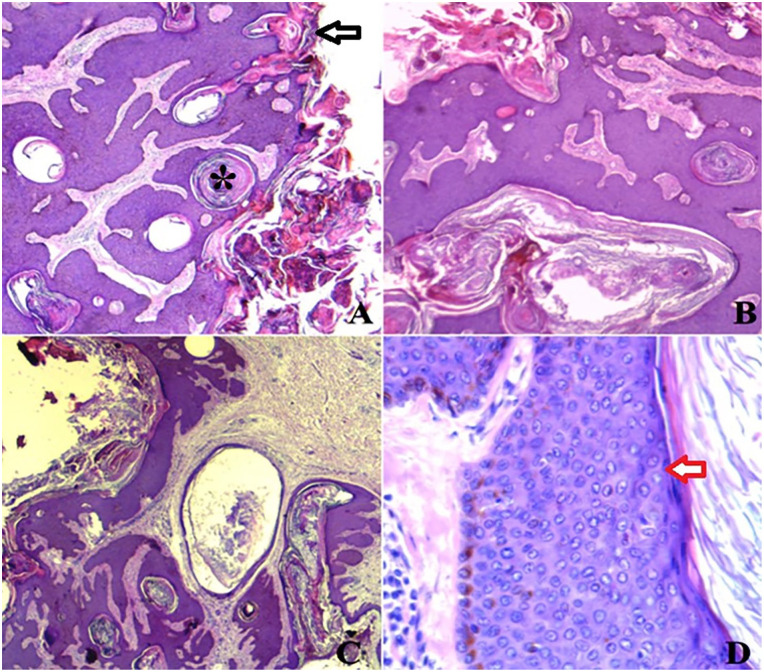

一名 75 岁的男子因腹部增大的无痛性皮肤肿瘤就诊,该肿瘤在过去 30 年中不断发展。既往病史无异常。体格检查显示,他的皮肤肿块呈褐色块状,表面呈不规则角化疣状,无分泌物或溃疡。临床推测该肿块为黑色素细胞瘤或疣状癌。对肿块进行了单块切除,结果良好。标本随后被送往病理科,以排除恶性肿瘤的可能性。显微镜检查发现,肿瘤呈褐色,大小为 7.5 × 7 × 1.5 厘米,有裂隙和菜花状外观。最终的组织学报告得出结论:这是一个巨大的脂溢性角化病。

A 75-year-old man presented with an abdominal enlarging painless tumor of the skin evolving over the last 30 years. His past medical history was unremarkable. Physical examination revealed a brownish pedunculated cutaneous mass which had an irregular keratotic warty surface with no discharge or ulceration. The mass was clinically presumed to be a melanocytic tumor, or a verrucous carcinoma. A monoblock excision of the mass was performed with a good outcome. The specimen was then sent to our pathology department to rule out malignancy. Macroscopic examination revealed a brownish tumor of 7.5 × 7 × 1.5 cm which had fissures and cauliflower-like appearance. Final histological report concluded to a giant seborrheic keratosis.